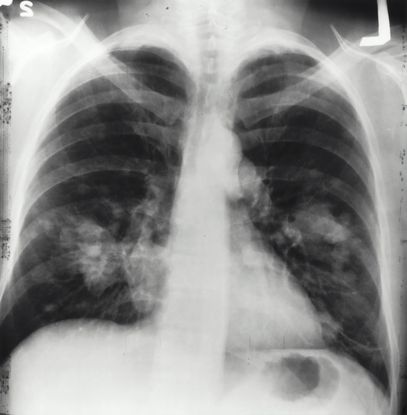

Felags krabbameinsmóttøka í Sjúkrahúsverkinum

Fyrstu gleðiligu tíðindini seinastu dagarnar eru, at felags krabbameinsmóttøka er sett á stovn í Sjúkrahúsverkinum. Hetta er fyri at staðfesta krabbameinssjúkuna og fáa sjúklingin í viðgerð, so skjótt sum til ber.

Góði Jan Rasmussen og tit í Sjúkrahúsverkinum! Takk fyri tykkara áræði og áhaldni. Hetta er fyrsta stigið og hetta er eitt ógvuliga týðandi stig.

Nú bíða vit spent, til Løgtingið tekur næsta stigið og fer at seta lóg í gildi um viðgerðartrygd. Lógin skal áseta, hvør mest loyvda bíðitíðin skal vera hjá okkum føroyingum til ávikavist at verða útgreinað og at fáa viðgerð fyri krabbamein.